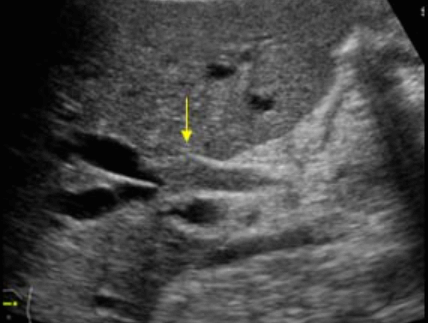

미리찌 증후군 (Mirizzi's syndrom) Mirizzi's syndrom 은 담낭경부, Hartmann's pouch 혹은 담낭관의 결석에 의해 총 간관(CHD)이 폐쇄되는 질환이다. 총 간관(CHD)이 협착되면서 상부담관은 확장되고 하부담관의 직경은 정상으로 나타난다. 증상은 폐쇄성 황달, 복부통증, 발열 등이 나타난다. 급성담낭염이 있으면서 담관폐쇄를 동반할 경우 의심해 볼 수 있다. 담낭절제술 후에 남아있는 담낭관의 결석이 총 간관(CHD)을 직접 누르거나 염증성 협착을 유발하기도 한다.

US finding

- 담낭관 또는 담낭 경부에 결석이 확인된다.

- 총간관(CHD) 또는 담낭관(cystic duct)의 확장소견이 보인다.

- 간내외 담관의 확장이 관찰된다.